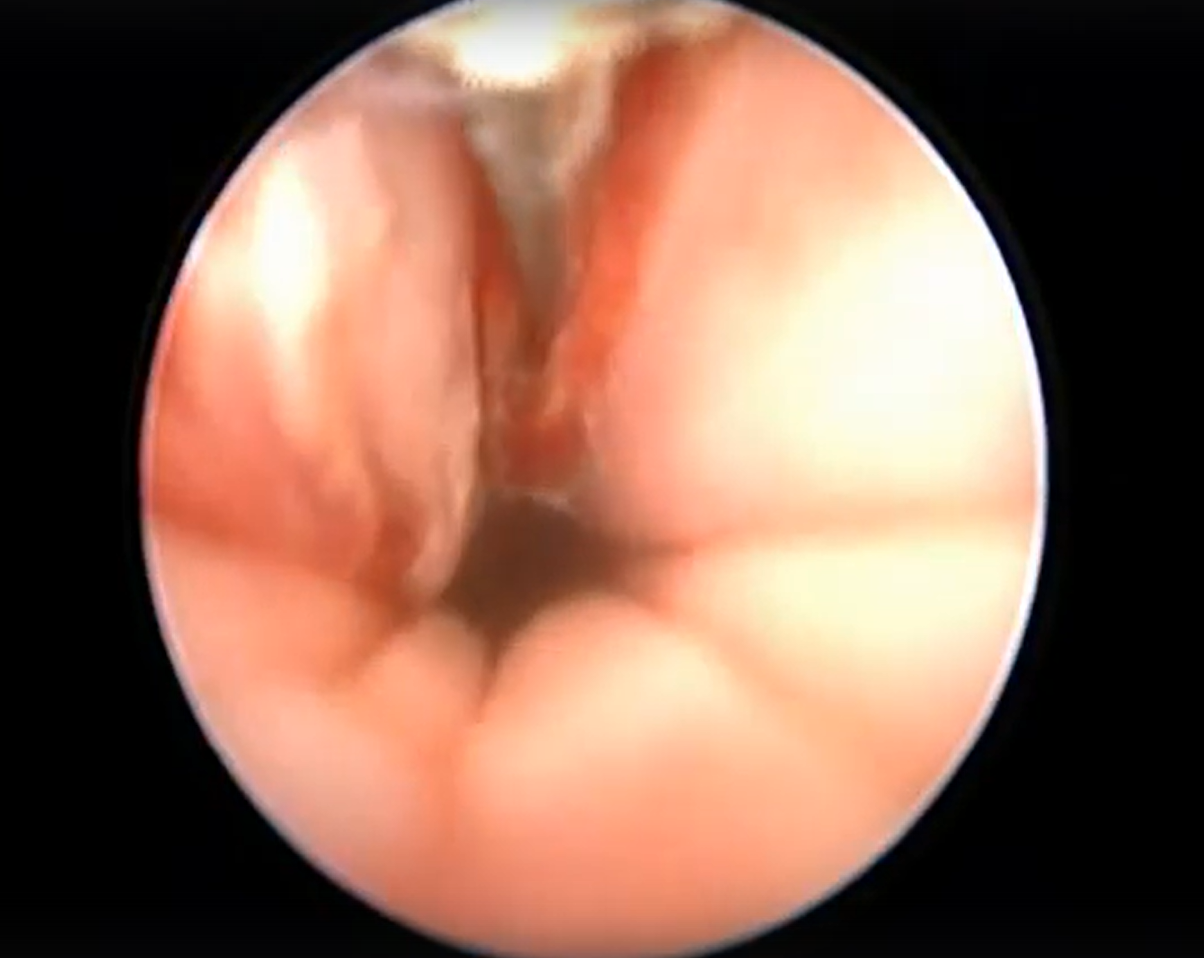

Сегодня на приеме у Сергея Владимировича была интересная находка. У собаки породы Йоркширский терьер при проведении вагиноскопии выявлено новообразование на вентральной стенке влагалища.

Питомец поступил с жалобами на кровянистые выделения из вульвы, ранее собака была стерилизована. Вагиноскопия - важный метод диагностики и лечения проблем репродуктологии. Видео с объектива эндоскопа можно посмотреть по ссылке https://vk.com/wall-232218233_16

После вчерашней находки при проведении вагиноскопии у собаки Йоркширский терьера было проведено удаление новообразования в области влагалища с использованием монополярной коагуляции и диссекции с последующей абляцией тканей слизистой влагалища. Метод - вагиноскопия в водной оптической среде (стерильный раствор дистиллированной воды)

Это малоинвазивный способ хирургии, являющийся малотравматичным, обеспечивающим современный подход к патологиям репротракта. После данной манипуляции травматизм минимальный - происходит быстрое восстановление питомца без видимых клинических проявлений Видео с объектива эндоскопа можно посмотреть по ссылке https://vk.com/wall-232218233_17